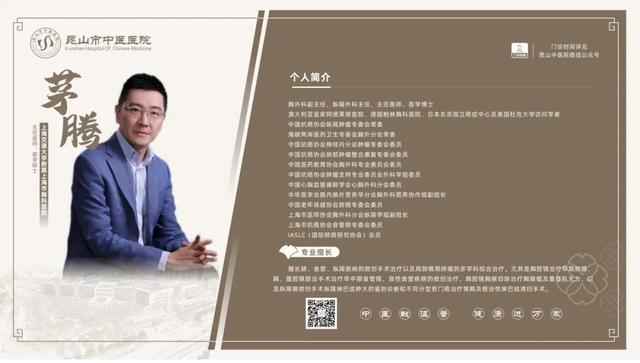

6��23��-6��29��������ר�ҳ���һ����

6��23��-6��29�������dz���ר�ҽ���